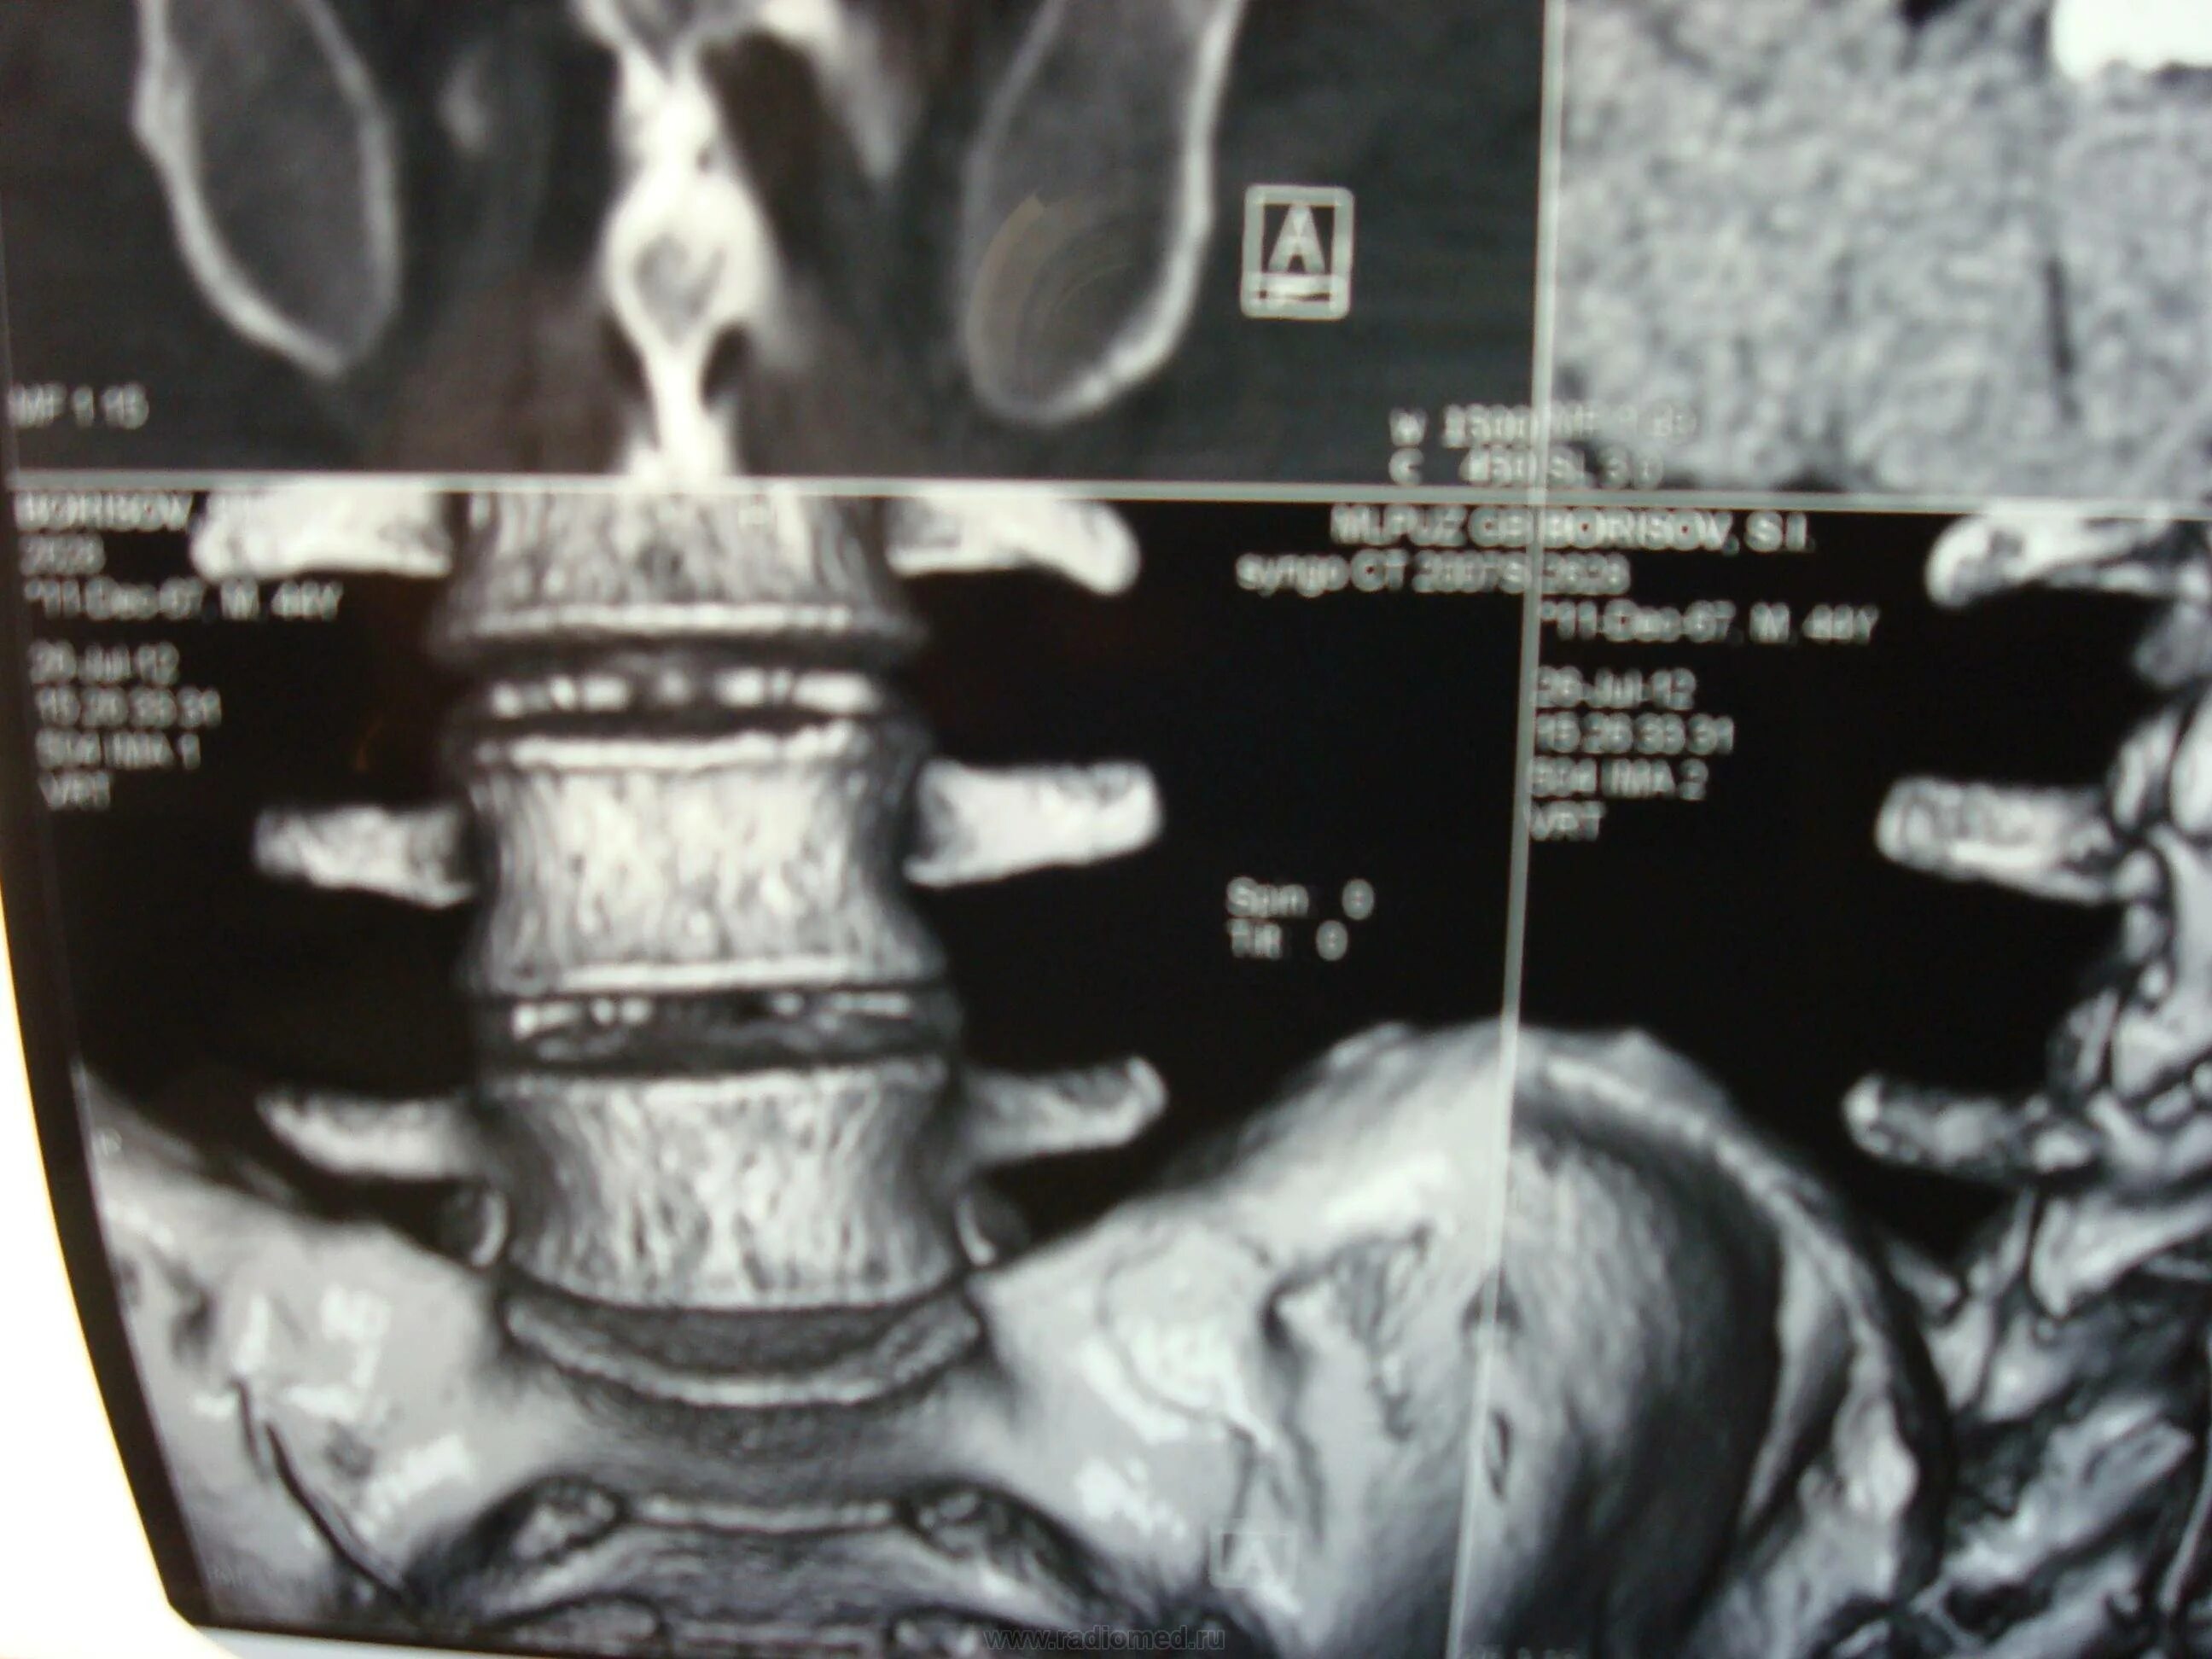

Мрт пояснично крестцового отдела тазобедренные суставы